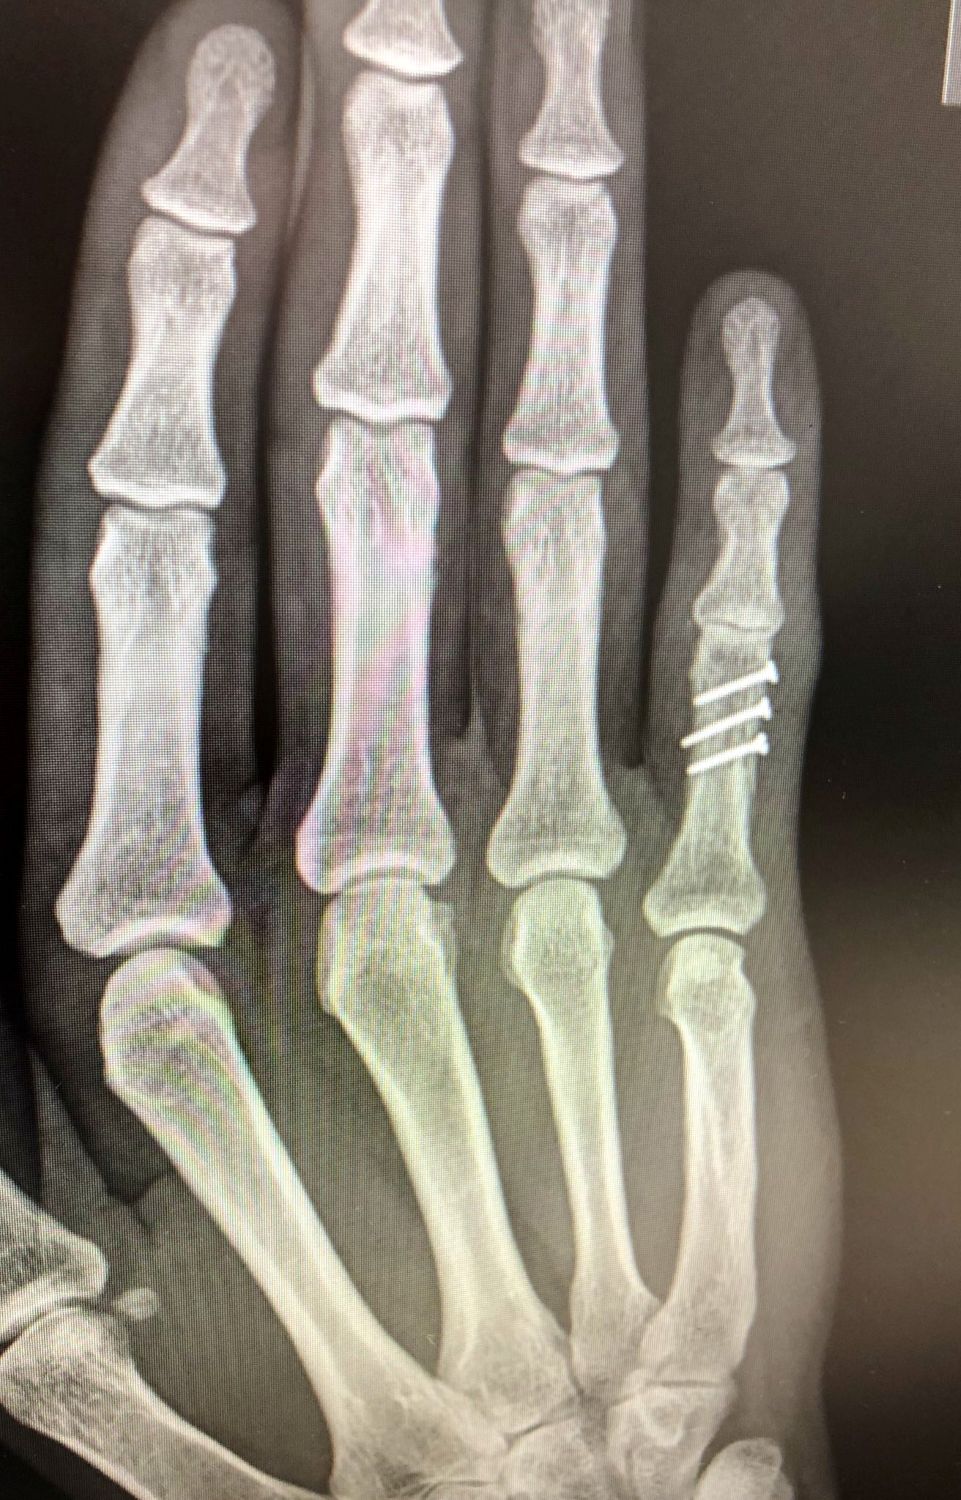

PATOLOGÍAS EN MANO Y DEDOS - FRACTURAS DE LA MANO Figura 1 - Fractura falange proximal 4º dedo

Figura 1 - Fractura falange proximal 4º dedo.(Ver también Figura 5)

Algunas fracturas pueden ser sencillas, en las que los fragmentos de huesos están alineados y estables. Otras son más complejas: son inestables y los fragmentos de hueso tienden a desplazarse: hundirse, girarse, angularse…(Figuras 1, 2 y 3).

FRACTURAS DE LA MANO Figura 5 - Osteosíntesis con placa fractura falange proximal 4º dedo

Figura 5 - Osteosíntesis con placa fractura falange proximal 4º dedo.